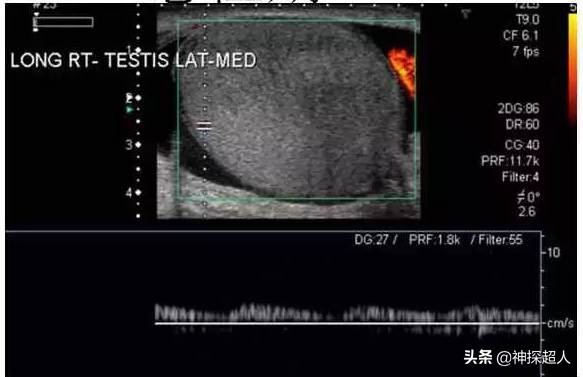

患者:男,28岁

病史:右侧阴囊突然疼痛5小时。

超声检查过程中的体格检查:患者右侧阴囊稍肿大,外部皮肤无红肿、破溃,触摸*丸睾**质地较硬,轻触痛。

超声检查提示:*丸睾**肿胀近似球形,回声减低,CDFI于*丸睾**内未探及血流信号。

术中探查:左侧*丸睾**呈紫黑色,精索与*丸睾**连接部粘连明显,呈360度扭转,将*丸睾**精索复位,温盐水纱布湿敷,观察10分钟颜色无变化,切开*丸睾**可见暗黑色血性液流出,无活动性出血,考虑*丸睾**完全坏死。